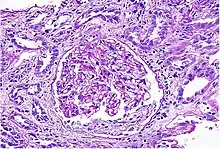

Acute interstitial nephritis on light microscopy

While non-invasive patient evaluation (physical examination, blood and urine testing, imaging studies) can be suggestive, the only way to definitively diagnosis interstitial nephritis is with a tissue diagnosis obtained by kidney biopsy. Pathologic examination will reveal the presence of interstitial edema and inflammatory infiltration with various white blood cells, including neutrophils, eosinophils, and lymphocytes. Generally, blood vessels and glomeruli are not affected. Electron microscopy shows mitochondrial damage in the tubular epithelial cells, vacuoles in the cytoplasm, and enlarged endoplasmic reticulum.[23]